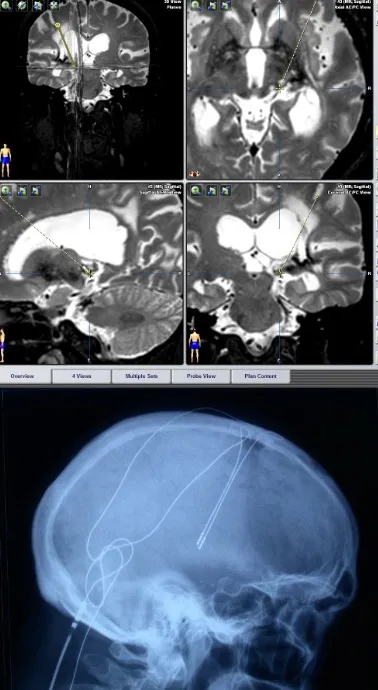

Estimulación cerebral profunda

Podemos intentar llegar al centro del cerebro, al tálamo, y colocar electrodos de estimulación. Obviamente, estos procedimientos requieren equipos muy bien coordinados de neurofisiología y neurocirugía, que conozcan perfectamente el abordaje de los diferentes núcleos a nivel talámico.

Es realmente una simbología muy compleja de estimulación cerebral profunda. También se puede colocar el electrodo en el cíngulo, y según el tipo de dolor, si es nociceptivo o neuropático, se elige un núcleo u otro para la estimulación.

Estimulación de la corteza motora

Curiosamente, también funciona la estimulación de la corteza cerebral, específicamente de la corteza motora. Se colocan mallas de electrodos de este tipo sobre la corteza y se mantiene con una especie de marcapasos una estimulación continua.

Esta estimulación de la corteza motora va fundamentalmente dirigida a los dolores por desaferentización. Todas estas técnicas representan opciones terapéuticas que, según el tipo y localización del dolor, pueden ofrecer alivio significativo a los pacientes.